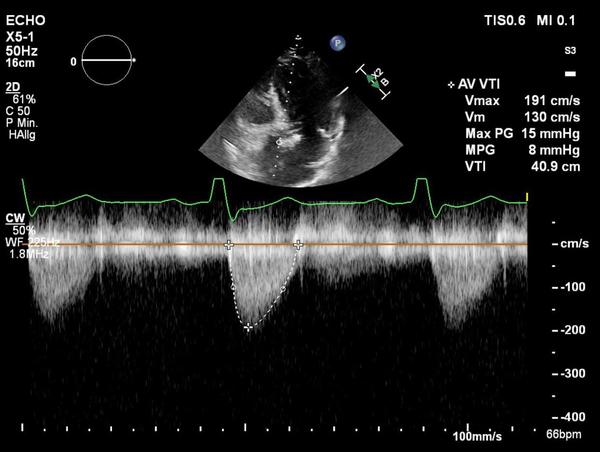

Anschließend wurde das korrekte Crimpen der Navitor Vision 25 mm unter Durchleuchtung überprüft. In einer C-Bogen-Angulation mit Exposition des LCA Ostiums (LCA-view: LAO 31 CRA 10) erfolgte eine Prädilatation der nativen Aortenklappe mit einem 20 mm semi-compliant Ballon (VACS III) unter ventrikulärer Schrittmacherstimulation (180-200/min). Während der vollständigen Balloninflation erfolgte eine Aortographie, die eine ausreichende Distanz zwischen der linken Taschenklappe und dem LCA Ostium zeigte. Die Länge der linkskoronaren Tasche erscheint kürzer als der Abstand des Anulus zur Koronararterie (Abbildung 8, Video 1).

Abbildung 8: Ballonprädilatation der Aortenklappe in "LCA-Ansicht"

Die Verwendung der "S-Kurve" der Annulusebene zur Identifizierung von Projektionen, die orthogonal zum Ostium der Koronararterien verlaufen, ist bei der Beurteilung des intraprozeduralen Risikos einer Koronarobstruktion hilfreich, da so die Ausdehnung der Taschenklappen während der Valvuloplastie und der simultanen Aortographie dargestellt werden können.